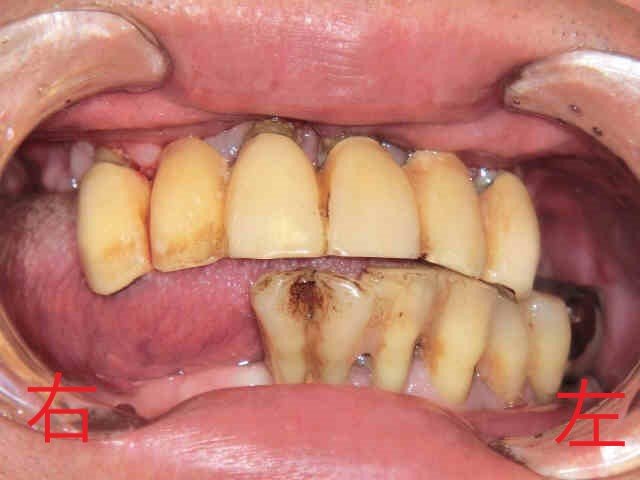

上記写真は、みらい歯科クリニックに来院された兵庫県三木市にお住まいの50代男性の口腔内を正面から撮影したものです。なお、写真の掲載には患者様の同意をいただいております。

患者様は、上のブリッジ(固定式の被せもの)が揺れて何もしていなくても痛みがあると訴えておられました。また、下の歯も歯周病が進行しており、揺れが強く抜歯が必要な状態でした。

下記写真は、同じ患者様の下顎の歯を撮影したものです。歯石が大量に付着し、歯周病がかなり進行していました。そのため歯を支える骨が失われ、歯根(歯の根)が露出しています。